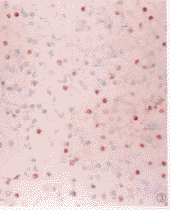

2.2 EB病毒检测 EBERs原位杂交17例T细胞淋巴瘤中11例(64.7%)阳性,6例阴性。4例B细胞淋巴瘤均阴性。阳性信号位于肿瘤细胞核内,呈深蓝紫色,分布于10%~80%的瘤细胞核内(图3),阳性病例均为中~大T细胞淋巴瘤,且均有血管浸润,2例伴有明显坏死。

图3 鼻烟部中-大T细胞性淋巴瘤,EBV原位杂交,阳性细胞呈蓝紫色 .×200